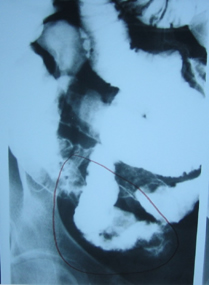

Στους ίδιους ασθενείς η εντερόκλυση μπορεί να αναδείξει ανάλογα ευρήματα με την ενδοσκοπική κάψουλα (εικόνες 36-43) ή να είναι φυσιολογική (εικόνες 44-48).

42  43

Εικόνα 42. Ο ίδιος ασθενής με την εικόνα 11.                Εικόνα 43. Ίδιος ασθενής με τις εικόνες 18-20.

Οδόντωση τελικού ειλεού από πολλαπλά                      Οίδημα και έλκη τελικού ειλεού

έλκη